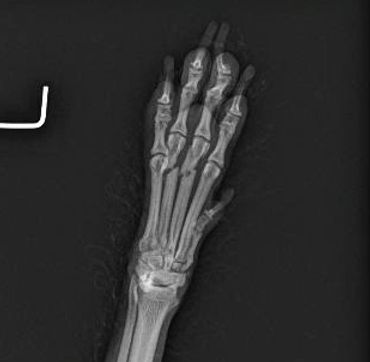

Radiology allows us to see spacial relationships of your pet's internal organs. We evaluate size and position to accurately diagnose internal problems. Radiology also allows us to evaluate orthopedic conditions with detail.